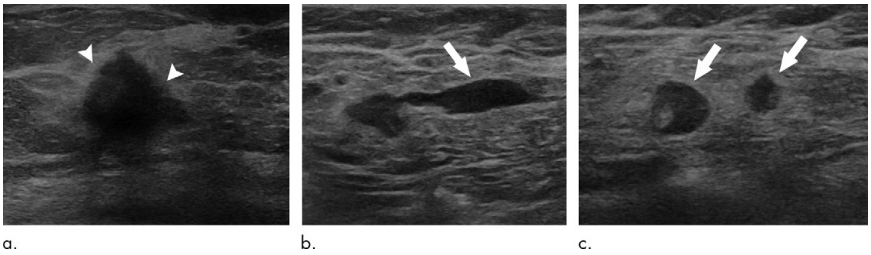

图1.一例T2N2M0期HR+/HER2-乳腺癌患者的腋窝超声表现[3]

准确评估腋窝淋巴结状态对于确定肿瘤分期、制定个体化治疗方案以及预测患者预后具有至关重要的意义。在临床实践中,腋窝超声作为一种非侵入性、无辐射、可重复的检查手段,被广泛应用于乳腺癌腋窝淋巴结的评估。然而,其临床价值和应用效果在不同地区和研究中存在差异,例如欧洲已常规使用AUS术前评估腋窝淋巴结,而美国仅用于查体腋窝阳性以及拟行新辅助治疗的患者[3-4]。这种差异反映了不同地区在乳腺癌诊断和治疗策略上的不同理念和实践。